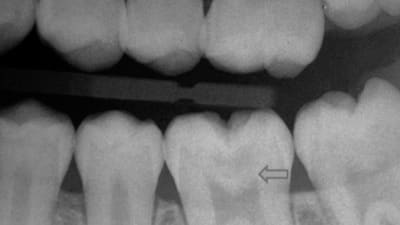

Case Reports Periodontics Techniques for Preserving Pulp Vitality in an Asymptomatic Deep Carious Lesion: A Clinical Case Study By Christine Nguyen, Sue Chhay, DDS September 01, 2022 11 min read